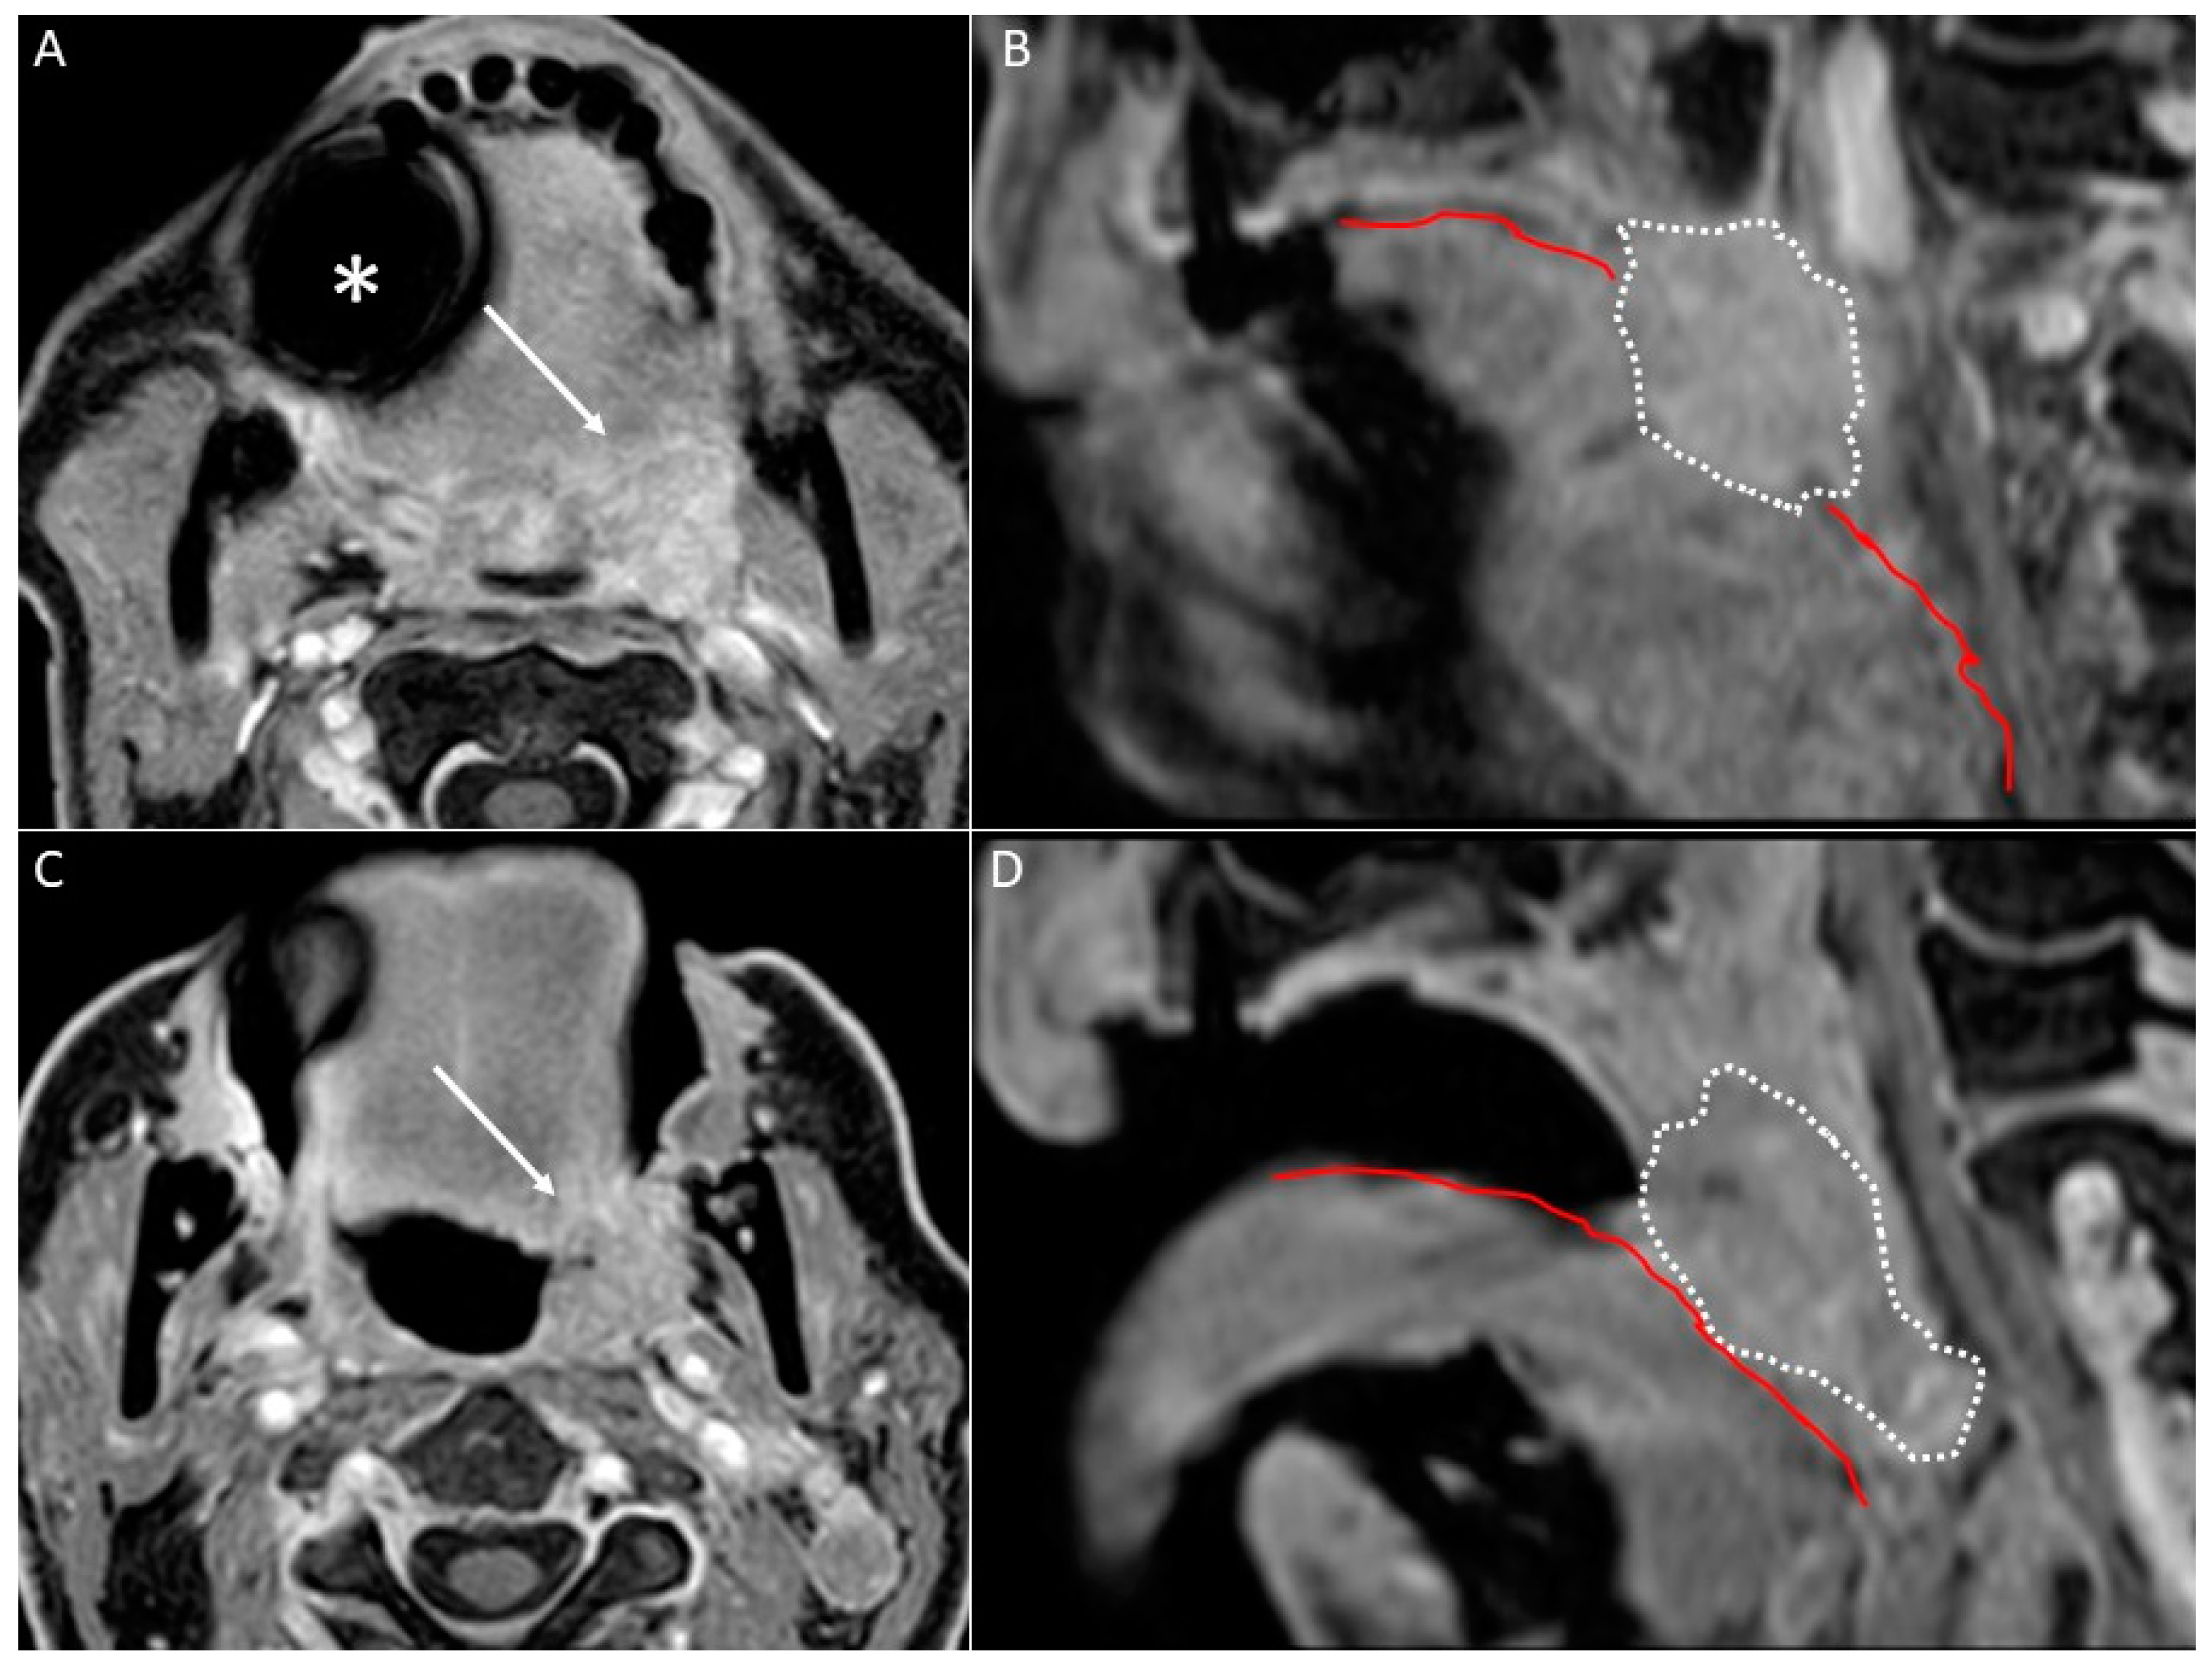

- Open mouth technique. Patients open their mouth and the acquisition is obtained with quiet respiration. A device (i.e., a 50 mL syringe) can be used between teeth to ensure the maintenance of the right position [28]. It allows the separation of the palatal mucosa from the muscular component of the tongue clarifying the exact origin, infiltration, and thickness of tumoural masses (Figure 12 and Figure 13).